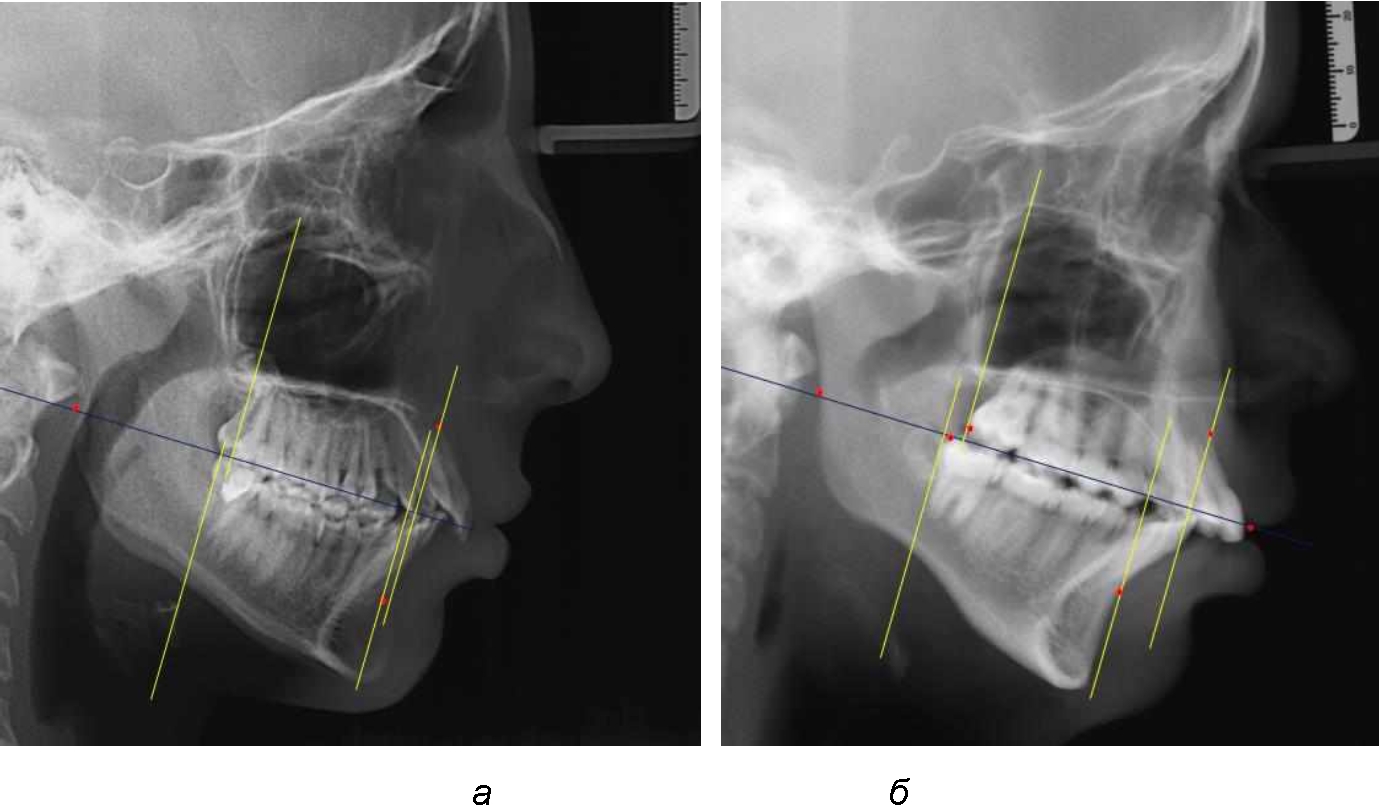

Аналогичное расстояние было отмечено и при расположении дистальных окклюзионных точек верхней и нижней челюсти (рис. 2).

Рис. 2. Положение апикальных точек и челюстей при нормопозиции (а), антепозиции (б) и ретропозиции (в) верхней челюсти